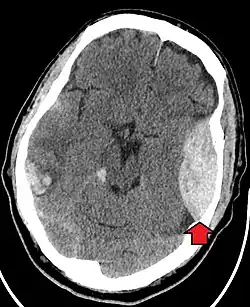

Blunt cranial trauma

The primary clinical concern with blunt trauma to the head is damage to the brain, although other structures, including the skull, face, orbits, and neck are also at risk.[8] Following assessment of the patient's airway, circulation, and breathing, a cervical collar may be placed if there is suspicion of trauma to the neck. Evaluation of blunt trauma to the head continues with the secondary survey for evidence of cranial trauma, including bruises, contusions, lacerations, and abrasions. In addition to noting external injury, a comprehensive neurologic exam is typically performed to assess for damage to the brain. Depending on the mechanism of injury and examination, a CT scan of the skull and brain may be ordered. This is typically done to assess for blood within the skull or fracture of the skull bones.[17]

Traumatic brain injury (TBI)

Traumatic brain injury (TBI) is a significant cause of morbidity and mortality and is most commonly caused by falls, motor vehicle crashes, sports- and work-related injuries, and assaults. It is the most common cause of death in patients under the age of 25. TBI is graded from mild to severe, with greater severity correlating with increased morbidity and mortality.[17][18]

Most patients with more severe traumatic brain injury have a combination of intracranial injuries, which can include diffuse axonal injury, cerebral contusions, and intracranial bleeding, including subarachnoid hemorrhage, subdural hematoma, epidural hematoma, and intraparenchymal hemorrhage.[8][17] The recovery of brain function following a traumatic injury is highly variable and depends upon the specific intracranial injuries that occur. However, there is a significant correlation between the severity of the initial insult as well as the level of neurologic function during the initial assessment and the level of lasting neurologic deficits.[17] Initial treatment may be targeted at reducing the intracranial pressure if there is concern for swelling or bleeding within the skull. This may require surgery, such as a hemicraniectomy, in which part of the skull is removed.[8][17]